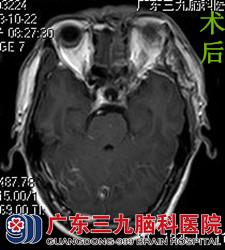

唐先生马上联系在广东三九脑科医院工作的侄儿,在侄儿的帮助下到医院行头颅MR检查,结果提示左侧眶尖区(肌锥外)示一不规则形异常信号影,增强后部分呈明显强化。综合神经外科的鲁明主任考虑脑膜瘤可能性大。在完善相关检查后,由鲁明主任主刀,在全麻及神经导航下行左侧视神经管探查+眶尖病变切除术,术中显微镜下见病变呈红褐色,伴有出血,边界不清,予分块切除,手术顺利结束。术后经过专科治疗护理,唐先生左眼视物较术前好转,未出现手术并发症,康复出院。术后病理结果:毛细血管瘤。